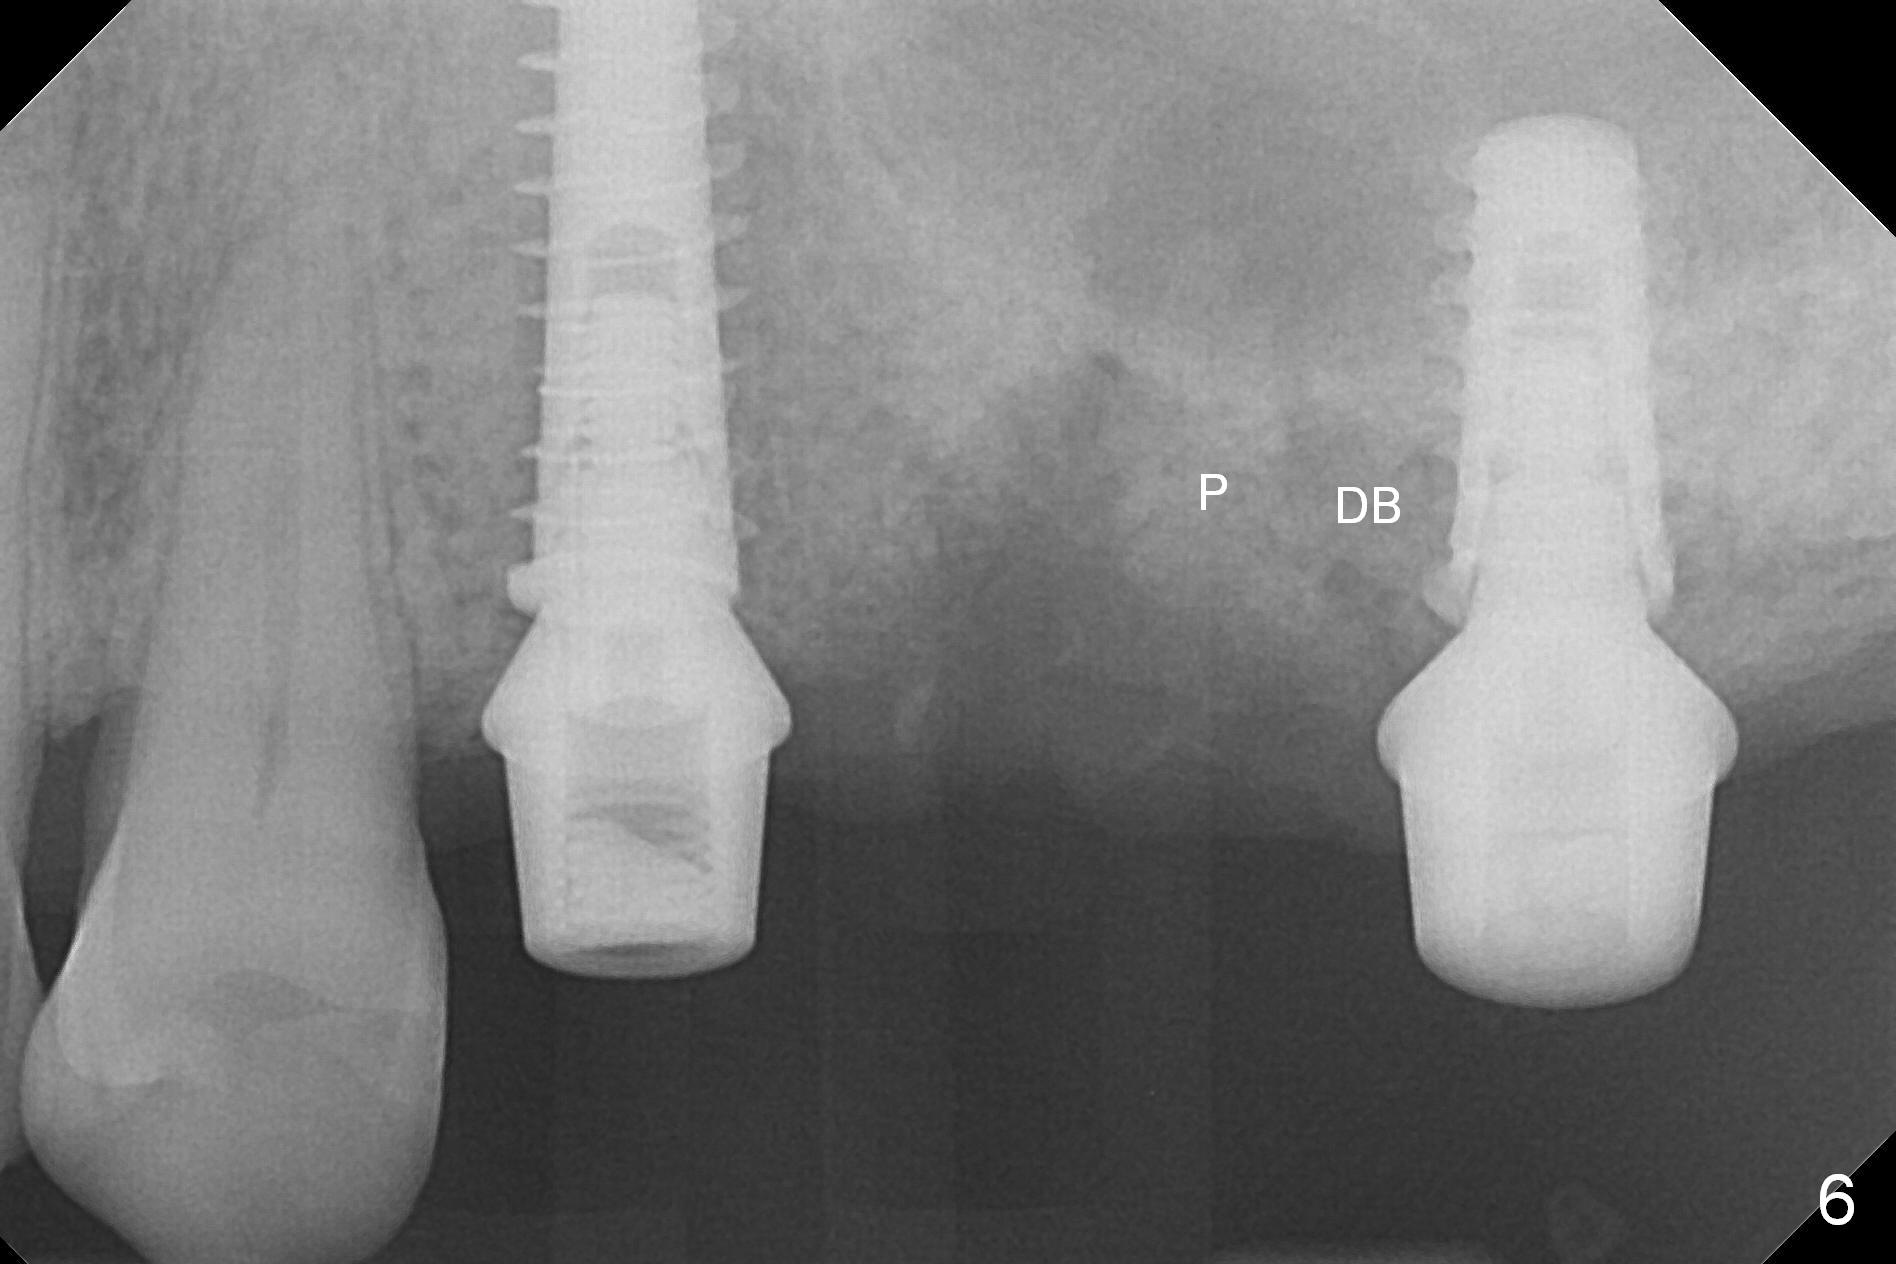

After placement of the remaining graft into the palatal (Fig.6,7 P) and distobuccal (DB) sockets of #14 and collagen plug into the 3 sockets of #14, abutments change to those with cuffs 1 mm shorter. The abutments are used to hold an immediate provisional bridge in place. The latter keeps the collagen plug and graft in place.

The fistula buccal to #14 remains 1 week postop (Fig.7) and disappears 1 months postop. The fistula does not re-appears 3 months postop with the implants at #13,15 apparently osteointegrated (Fig.8). With relining #13-15 provisional with increased vertical height (Fig.11), the patient has bilateral posterior contact (Fig.9), while the lower incisors do not contact the cinguli of the upper incisors (Fig.10 *). The space between the tooth #12 and the pontic #21 is unfavorable for posterior occlusal stability (Fig.11 *). Porcelain is chipped off the buccal surface of the pontic (Fig.12 *). If the patient does not afford an implant at #21 with redo crowns at #20 and 22 (Fig.13), what else could be done? He will return for #15 implant placement 4 months post socket preservation.